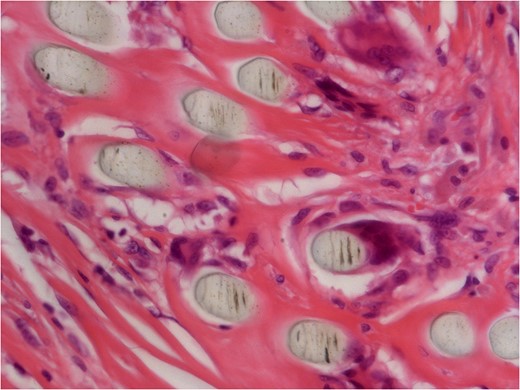

He underwent surgery to explore the tendon where an irregular, cystic, fibrofatty lesion was identified within the tendon (Figs 3–5). This was successfully resected and sent for histology which showed a florid granulomatous and histiocytic response to the suture material, in keeping with a suture granuloma (Figs 6 and 7). There was histological evidence of the abscess extending into the muscle (Fig. 8).

40× histology slide showing foreign body giant cell reaction to suture material.